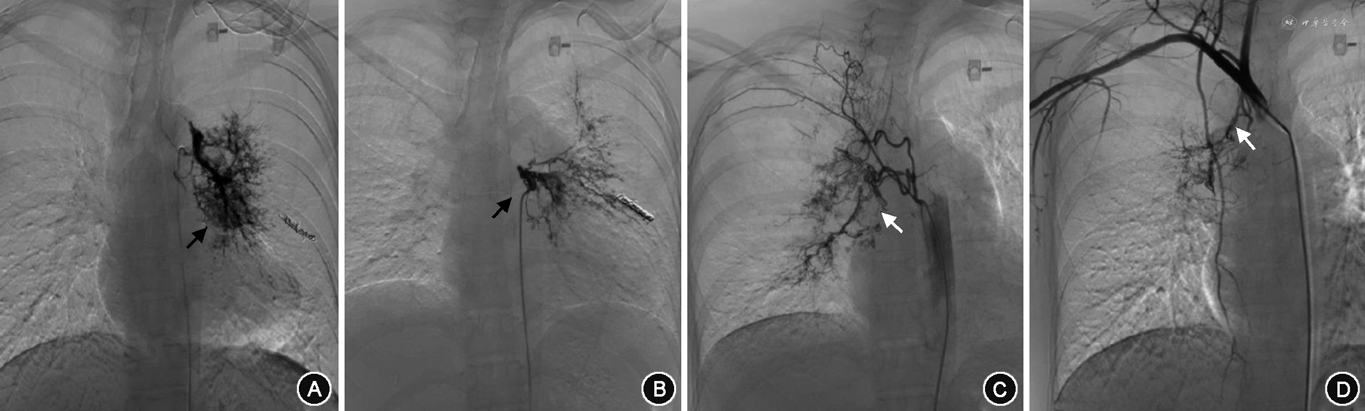

所有患者术中DSA均发现支气管动脉(bronchial artery,BA)血管增粗、迂曲,末梢分支增多紊乱,病灶区域血管呈网状或丛状分布(图2A),其中,29.6%为异位起源BA(图2B)。774例(63.9%)患者存在非支气管性体动脉(non-bronchial systemic artery,NBSA)异常并参与病灶部位供血(图2C)。1 092例(90.2%)患者存在体动脉-肺循环异常交通。包括肋间动脉-肺动脉瘘(图2C),食管固有动脉-肺动脉瘘(图2D);BA-肺静脉瘘(图2E);肺动-静脉瘘(图2F);143例(11.8%)有动脉瘤或瘤样扩张。包括支气管动脉瘤(图2G);非支气管性胸廓内动脉瘤(图2H);肺动脉假性动脉瘤(图2I)。单纯肺动脉高压引起的咯血,以第一大类先天性心脏病引起的肺动脉高压为常见,责任血管可涉及锁骨下动脉分支、胸、腹主动脉分支(支气管动脉、肋间后动脉、膈下动脉、食管固有动脉),主干迂曲增粗、末梢紊乱,责任血管床大多沿肺门周围分布(图3)。白塞病的靶血管分布在以肺动脉灌注较差位置的周围体动脉的迂曲、扩张及末梢紊乱,多发的体-肺动脉瘘形成,责任血管末梢网血管丰富(图4)。